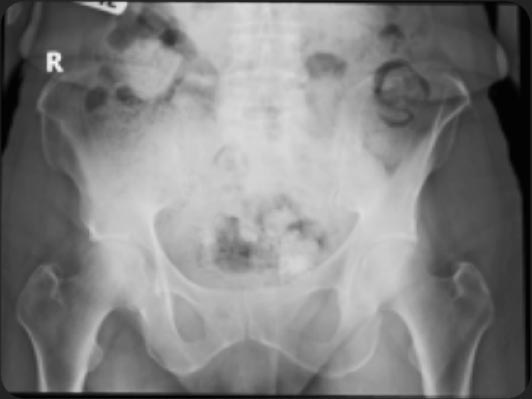

HIP POsitioning Assistant. HIPPO supports the objective and standardized measurement of the most important hip angles based on digital x-rays. These include, for example, the CCD and LCE angles as well as numerous other relevant angles.